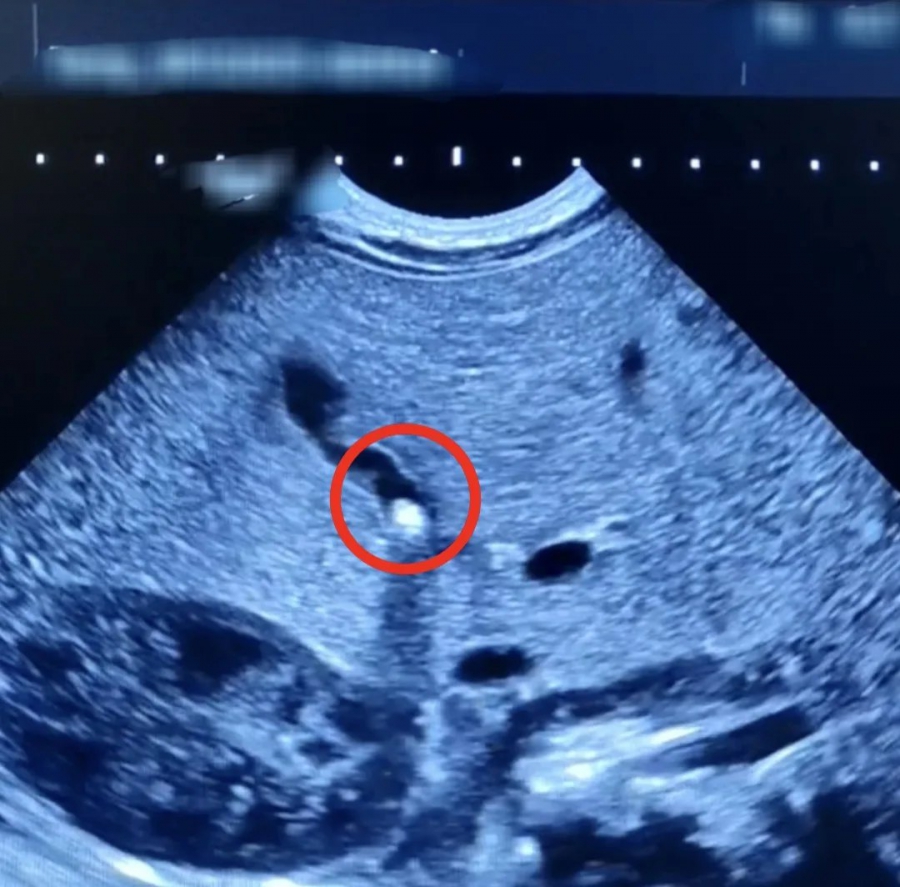

В Балаковской клинической больнице Саратовской области врачи провели операцию грудному ребенку, у которого обнаружили камень в желчном пузыре. Об этом рассказали в пресс-службе медучреждения.

Сообщается, что полуторамесячный малыш поступил в медучреждение по жалобам мамы на плохую прибавку массы тела и желтушное окрашивание кожи и склер у новорожденного. Обследование показало, что желчный проток младенца частично закрыт камнем небольших размеров.